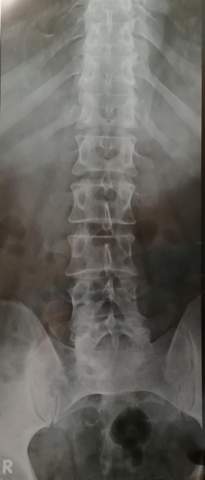

Jedoch muss die Krebserkrankung dafür groß genug sein. Bei genauerem Hinsehen lassen sich seitlich des Brustbeins sogar die Verästelungen der Bronchien sehen. Bei größeren Vorfällen bemerkt man allerdings eine Verschmälerung des Zwischenwirbelraums sprich.

Darstellung Von Wirbelsaule Und Gelenken Digitales Rontgen Und Mrt